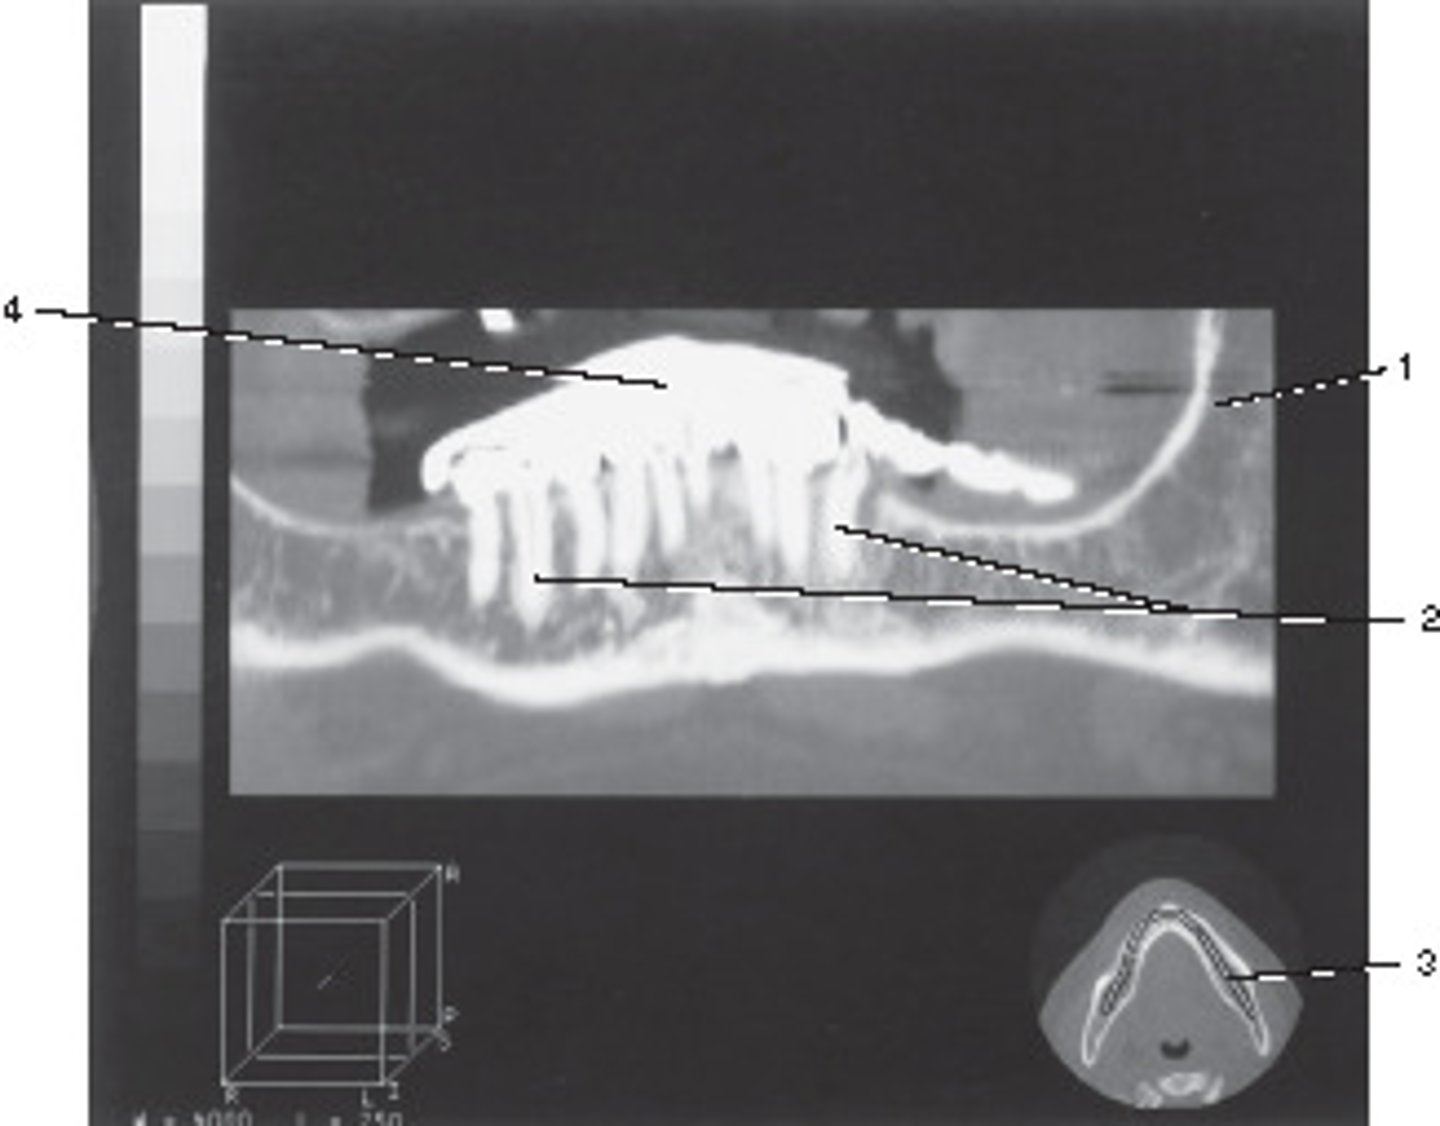

Oblique Axial Plane

This anatomic plane can best be described as the:

<p>This anatomic plane can best be described as the:</p>

Abdomen and Adomen/Pelvis

This localizer (scanogram) could be used to program which of the following examinations?

<p>This localizer (scanogram) could be used to program which of the following examinations?</p>